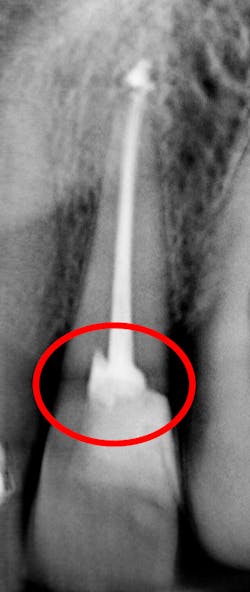

I see more complications and pathologies when using 3D tomosynthesis than I ever did with my old 2D images (figure 4). I can treat more because I can see more bone loss, interproximal caries, fractures, resorptions, abscesses, and more (figure 5).

In fact, twice today I was able to see something with Portray that wasn’t visible in the original 2D x-ray (figure 6). I don’t always take 2D images now, but I do when I think the case is straightforward or the patient has very little dental history. I often end up taking a tomosynthesis image just to be safe. With the 3D image I can scroll from buccal to lingual through the tooth and get much more data (figure 7). The new system has replaced my 2D PAs and bitewings.

Fortunately, 3D intraoral tomosynthesis found its way into the dental field. Based on the findings from a study out of the University of North Carolina, dentists who use 3D tomosynthesis for intraoral x-rays can detect approximately 36% more caries (figures 8 and 9).1 That’s tremendous!